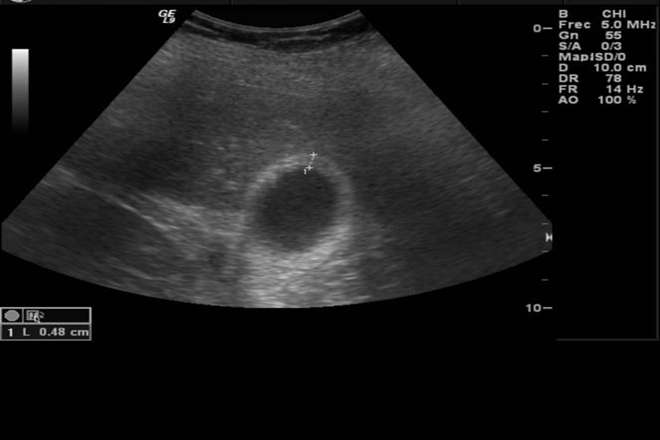

Según los hallazgos ultrasonográficos, se identificaron cinco grupos: edema de la pared (62 casos), apariencia normal (45 casos), litiasis (cinco casos), indeterminado (dos casos) y pólipo vesicular (un caso). El tamaño vesicular fue similar en todos los grupos (longitud 72 ± 9.8 mm y diámetro transversal 27.3 ± 6.6 mm). El grosor de la pared promedió 6.21 ± 3 mm en el grupo de edema, 2.1 ± 0.2 mm en el grupo de apariencia normal, 3 ± 1 mm en el grupo de litiasis y 2 mm en el grupo de pólipo vesicular. El contenido fue anecoico en 102 pacientes (88.7 %), con lodo biliar en 11 mujeres (9.6 %) y en dos casos no fue evaluable (1.7 %).

En resumen, las características ultrasonográficas más comunes de la vesícula biliar en pacientes con preeclampsia-eclampsia incluyen un órgano de dimensiones reducidas, paredes engrosadas por edema con frecuencia mostrando un «doble contorno» y contenido anecoico. Estos hallazgos deben interpretarse como parte de la preeclampsia-eclampsia y no como signos de enfermedad inflamatoria crónica de la vesícula biliar.